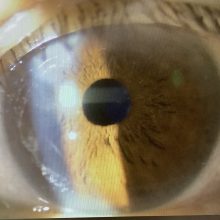

進行白内障の問題点

2024.02.24

今日は午前のみの外来で、手術の申し込みは、白内障2人、ICL1人、霰粒腫1人(49歳女性)でした。 今日、白内障の術前検査で受診された50代の女性の方は、水晶体が真っ白に濁った“成...